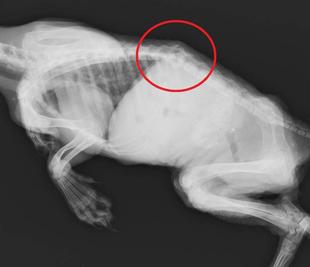

脊椎骨折のホンドタヌキ